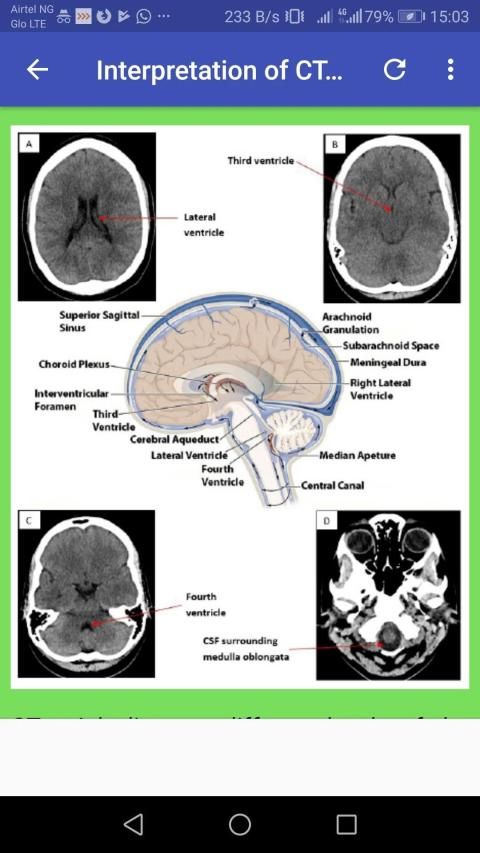

Computed tomography, more commonly known as a CT or CAT scan, is a diagnostic medical test that, like traditional x-rays, produces multiple images or pictures of the inside of the body.

The cross-sectional images generated during a CT scan can be reformatted in multiple planes, and can even generate three-dimensional images. These images can be viewed on a computer monitor, printed on film or by a 3D printer, or transferred to a CD or DVD.

CT images of internal organs, bones, soft tissue and blood vessels provide greater detail than traditional x-rays, particularly of soft tissues and blood vessels.

Computed tomography (CT) scanning of the head uses a series of x-rays of the head taken from many different directions; the resulting data is transformed into a series of cross sections of the brain using a computer program.